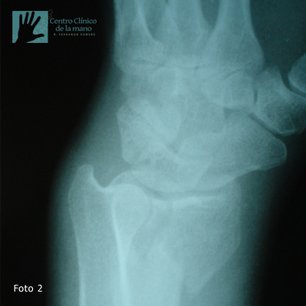

Fractura de Muñeca